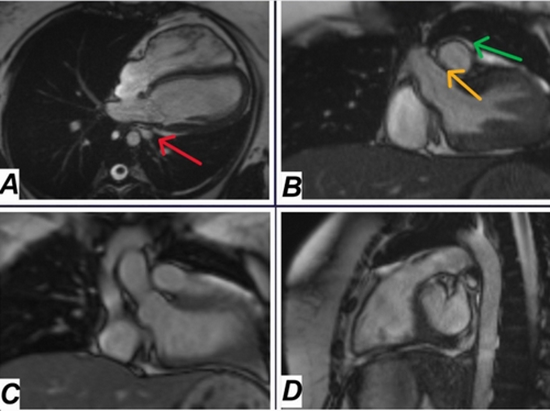

پزشکان ابتدا معاینه فیزیکی انجام دادند که طبیعی بود، سپس آزمایش‌های خون و نوار قلب (ECG) را بررسی کردند که تغییرات جزئی نشان داد. رادیوگرافی قفسه سینه (CXR) جابجایی قلب به سمت چپ را آشکار کرد. اکوکاردیوگرافی (TTE) موقعیت غیرعادی قلب را تایید کرد، اما برای تشخیص دقیق، از سی‌تی آنژیوگرافی (CTA) و ام‌آرآی قلب (CMRI) استفاده شد. این تصویربرداری‌ها نشان داد که پرده قلب سمت چپ کاملا غایب است، قلب به سمت چپ جابجا شده و ریه راست بیش از حد باد کرده، در حالی که ریه چپ کوچک‌تر است. خوشبختانه، هیچ عارضه‌ای مانند بیرون‌زدگی قلب یا فشار روی عروق وجود نداشت.